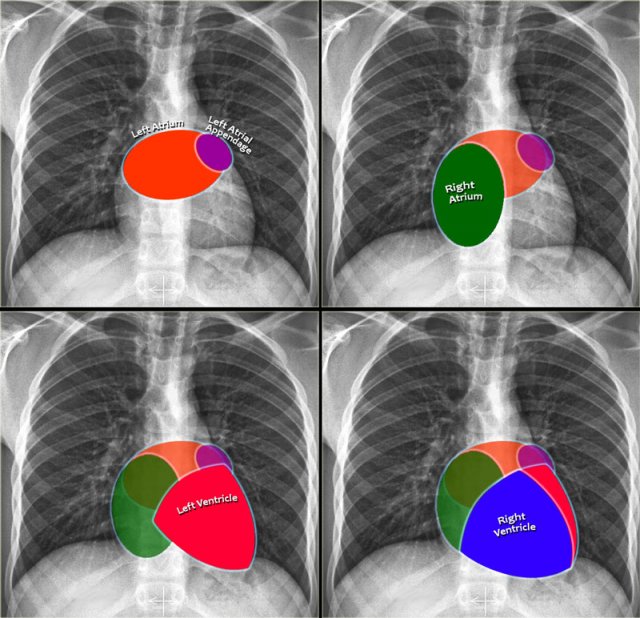

Cardiac Contours on Chest Radiography

On a standard chest radiograph, only the external contours of the heart are visible. In most cases, we can assess overall heart size and cardiac silhouette, but it is difficult to evaluate individual chambers. Nonetheless, understanding the anatomical positions of the cardiac compartments aids in interpreting shape and contour changes associated with chamber enlargement.

Left Atrium (LA)

It is the most posterior cardiac chamber and it receives oxygenated blood from the pulmonary veins, which enter the left atrium almost horizontally. The left atrial appendage is occasionally visible as a small outpouching just below the pulmonary trunk (best seen on lateral view).

Radiographic signs of left atrial enlargement:

• PA view: Bulging of the upper right heart border and widening of the carinal angle due to splaying of the main bronchi.

• Lateral view: Bulging of the posterior-superior cardiac contour.

Right Atrium (RA)

Receives deoxygenated blood from the superior and inferior vena cava.

Radiographic sign of right atrial enlargement:

• PA view: Outward displacement of the right heart border.

Left Ventricle (LV)

Is situated posterior and leftward to the right ventricle.

Radiographic signs of left ventricular enlargement:

• PA view: Leftward enlargement of the cardiac silhouette

• Lateral view: Bulging of the inferior-posterior contour of the heart.

Right Ventricle (RV)

Location: The most anterior chamber, directly posterior to the sternum.

Radiographic signs of right ventricular enlargement:

• PA view: Enlargement may push the heart silhouette leftward and in severe cases, the left heart border may be formed by the RV.

• Lateral view: Progressive filling of the retrosternal space, starting inferiorly and moving upward with increasing RV size.

Chamber-Specific Contours on Lateral View

• Left Atrium: Forms the upper posterior heart border; enlargement causes posterior bulging.

• Left Ventricle: Forms the lower posterior heart border; enlargement causes posteroinferior displacement.

• Right Ventricle: Occupies the lower retrosternal space; enlargement fills the retrosternal clear space superiorly.